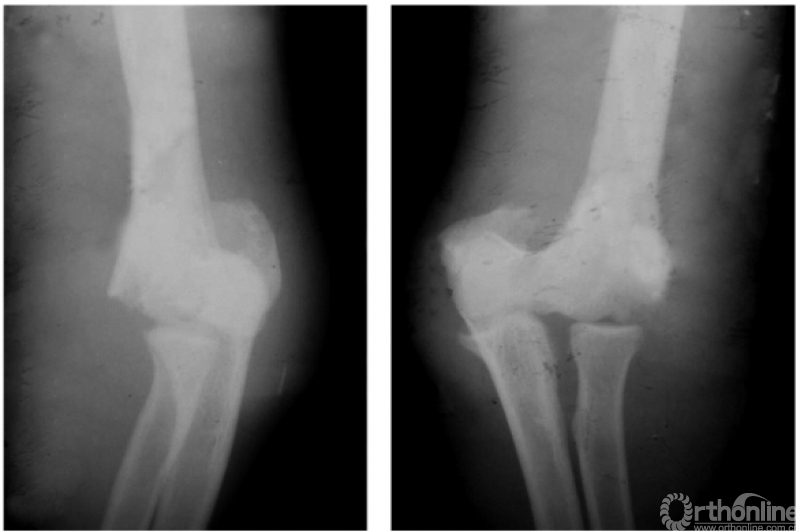

例2:伸展型肱骨髁上陈旧折,完全向后上移位的骨折远端,在被掀起的骨膜下成骨,已为肱骨下段重建了新的关系;而向前下移位的近折端已与尺骨近端形成骨性连接。致患肘被固定在肘曲40°位置上(图8)。

图8